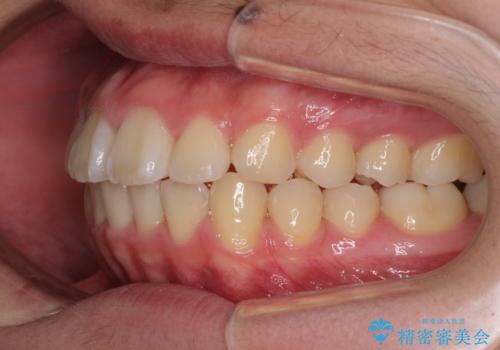

前歯のデコボコを短期間で治療 目立たないワイヤー矯正

- 矯正装置

- 審美装置

- 上下前歯のデコボコを改善したいとのことで来院された患者様です。

自己管理を減らしたいとのことで、ワイヤー装置による矯正治療を行うこととしました。

中学生と言うこともあり、1年強の短期間で終了しました。

歯磨きがしっかりとできないと虫歯になるリスクがありましたが、治療期間中は清潔な状態を保っていただけました。